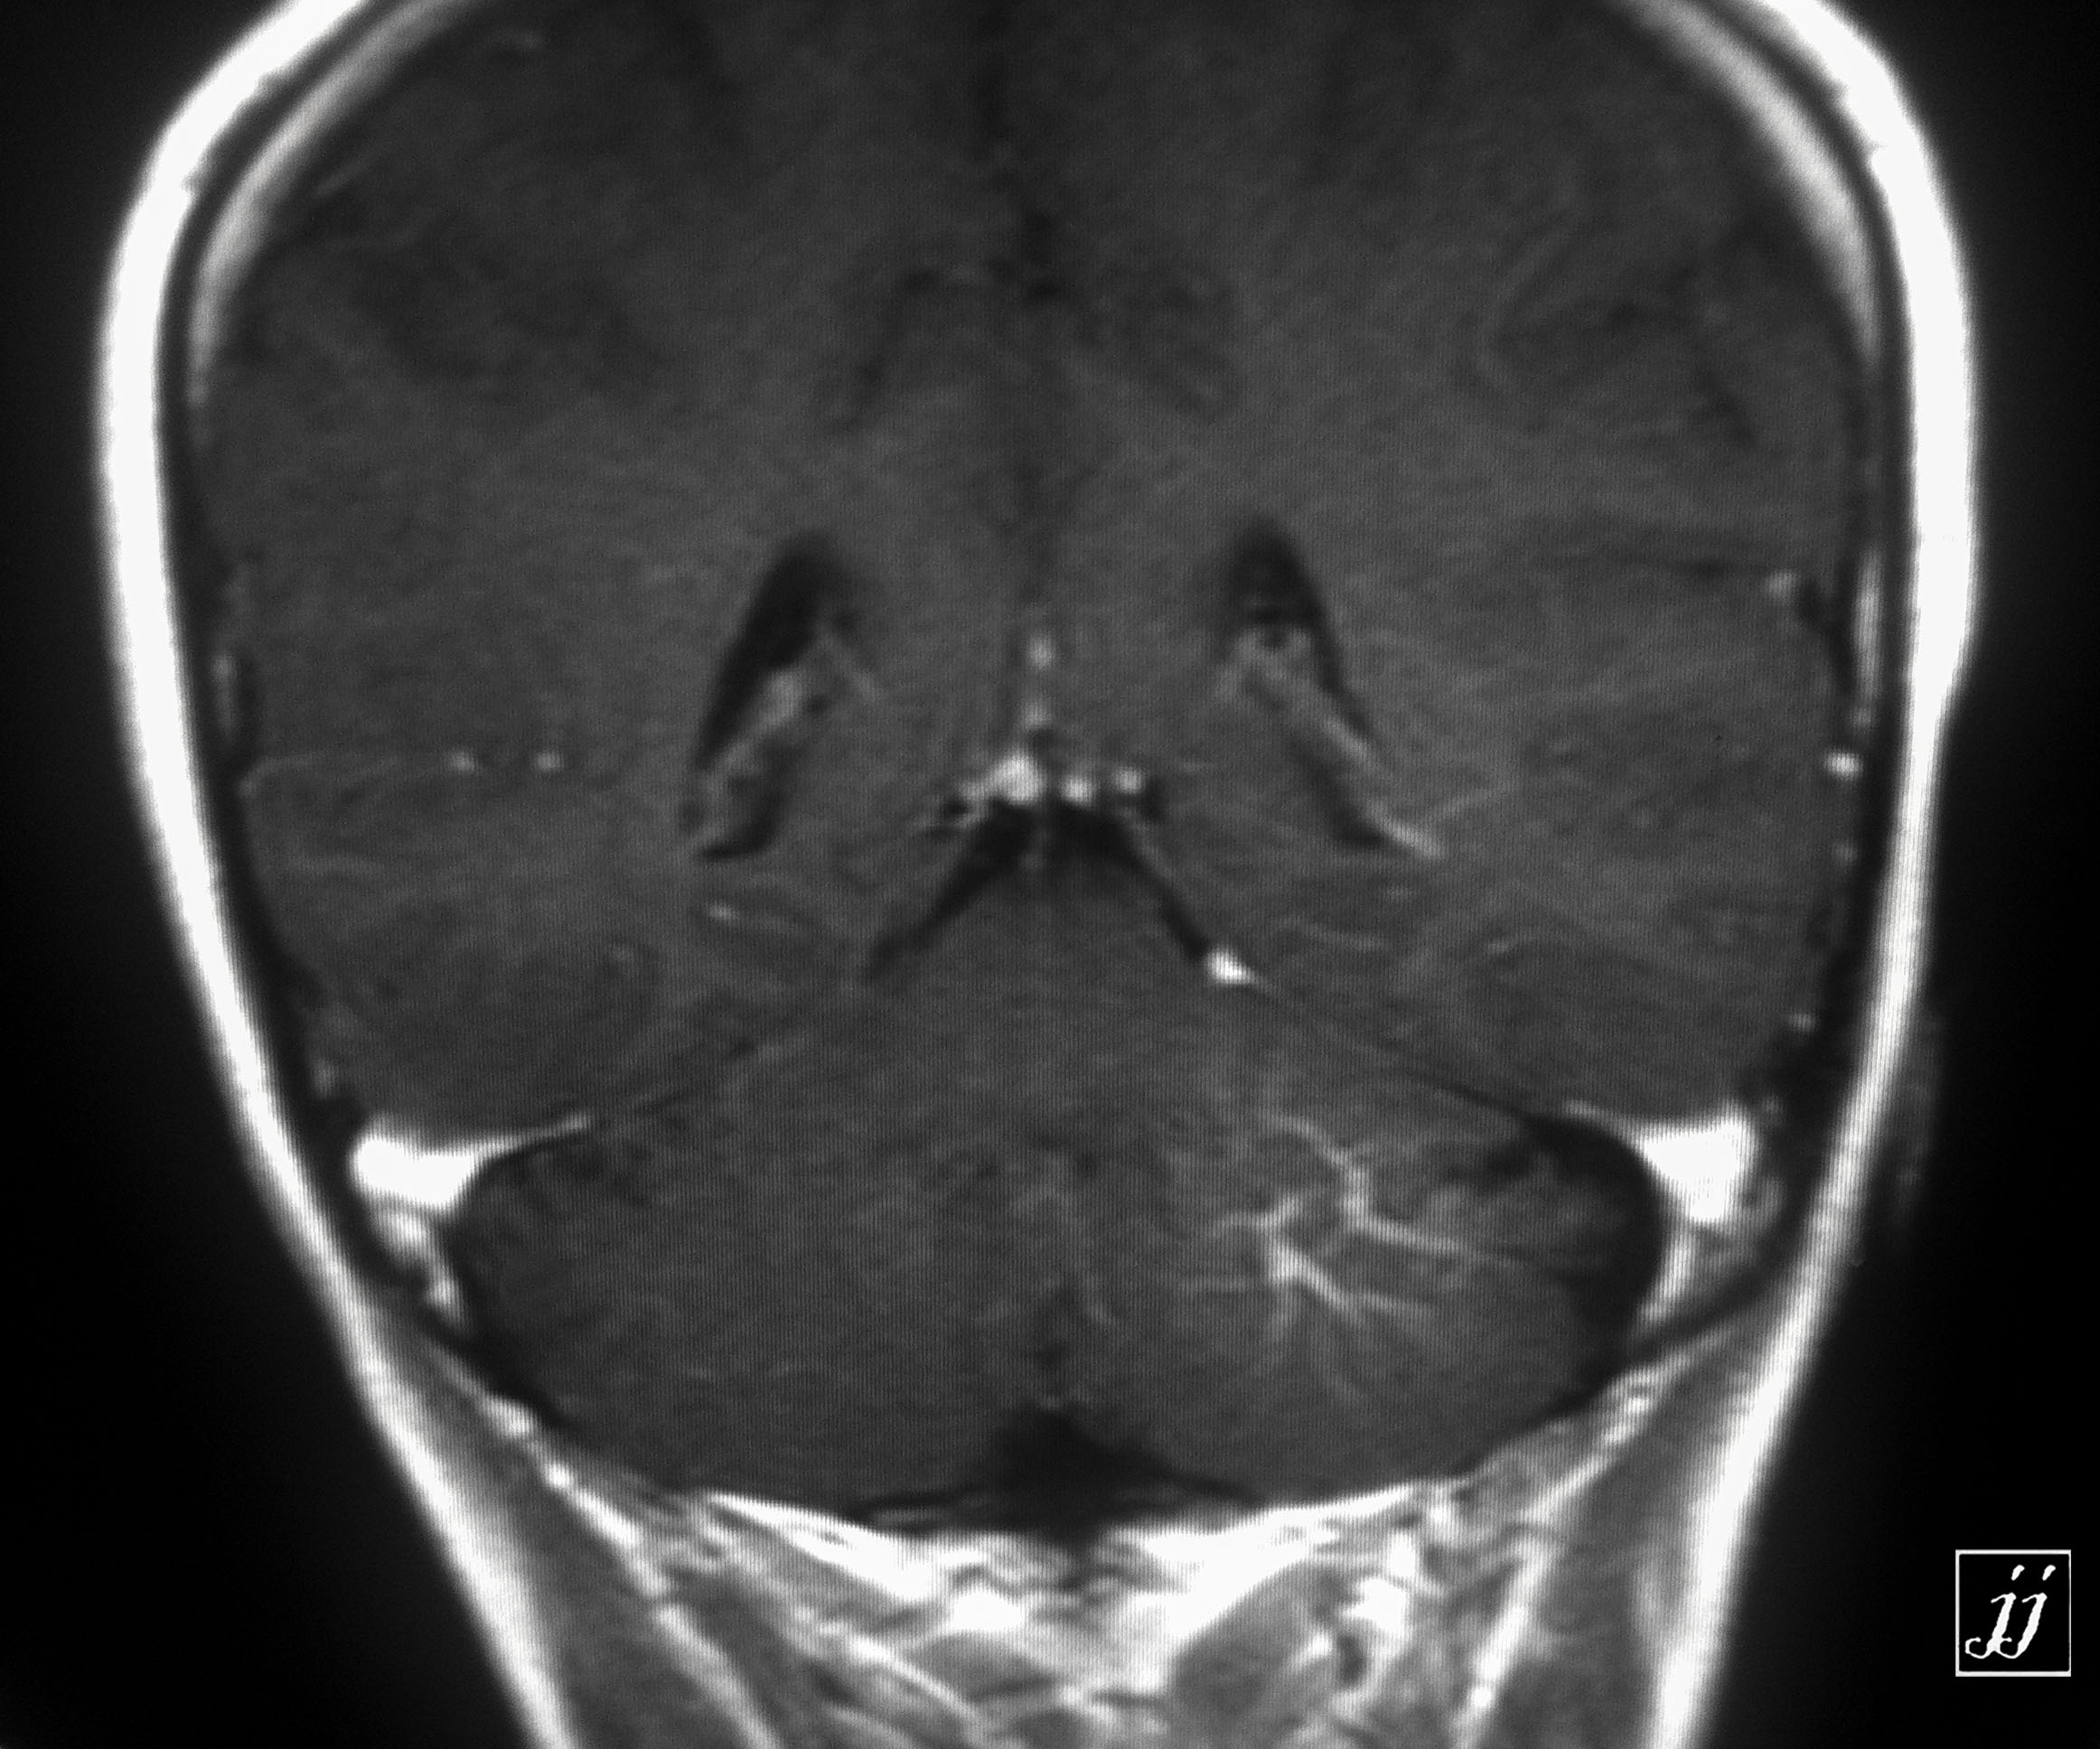

Brain- large left cerebellar venus angioma (2)